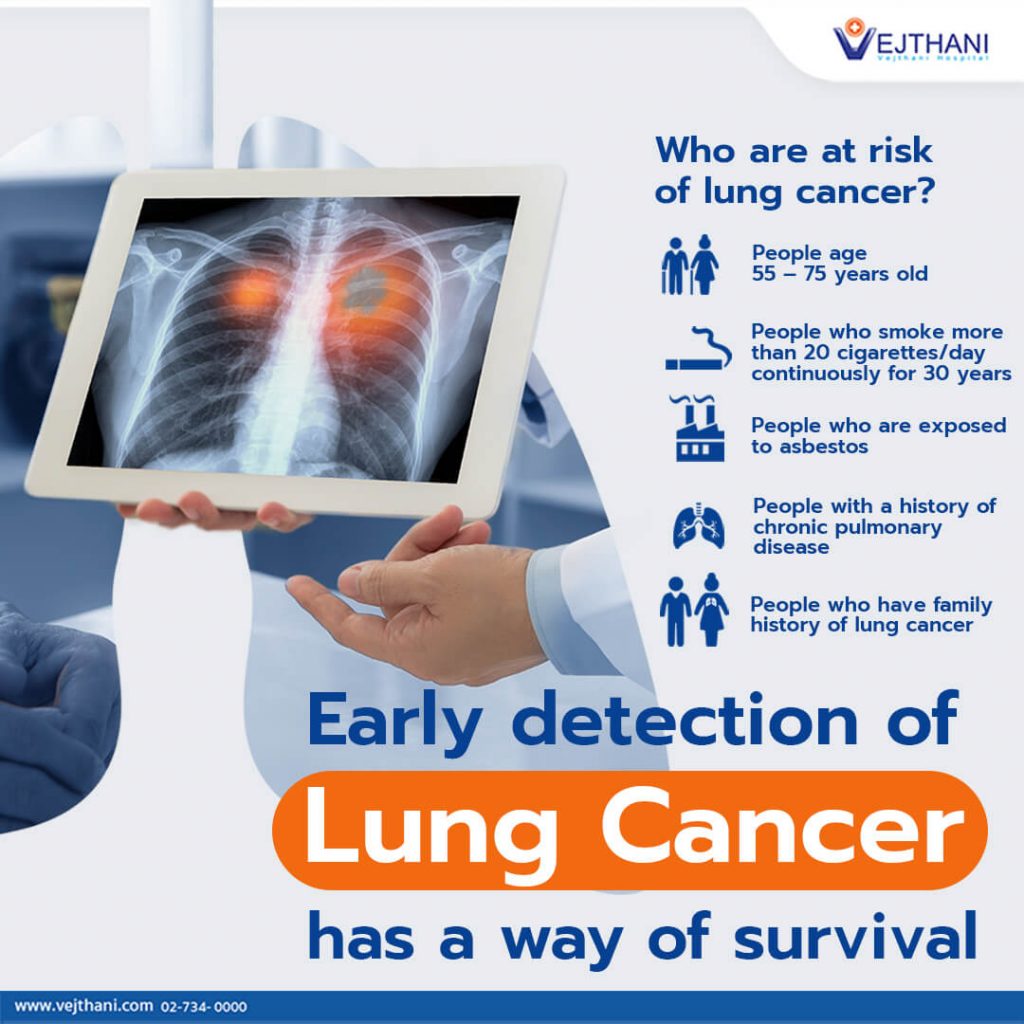

Lung Cancer Screening X Ray

Experience the clarity of Lung Cancer Screening X Ray with our curated collection of comprehensive galleries of images. featuring understated examples of photography, images, and pictures. designed to emphasize clarity and focus. Discover high-resolution Lung Cancer Screening X Ray images optimized for various applications. Suitable for various applications including web design, social media, personal projects, and digital content creation All Lung Cancer Screening X Ray images are available in high resolution with professional-grade quality, optimized for both digital and print applications, and include comprehensive metadata for easy organization and usage. Our Lung Cancer Screening X Ray gallery offers diverse visual resources to bring your ideas to life. Comprehensive tagging systems facilitate quick discovery of relevant Lung Cancer Screening X Ray content. Multiple resolution options ensure optimal performance across different platforms and applications. Time-saving browsing features help users locate ideal Lung Cancer Screening X Ray images quickly. The Lung Cancer Screening X Ray archive serves professionals, educators, and creatives across diverse industries. Instant download capabilities enable immediate access to chosen Lung Cancer Screening X Ray images. Whether for commercial projects or personal use, our Lung Cancer Screening X Ray collection delivers consistent excellence. Professional licensing options accommodate both commercial and educational usage requirements.